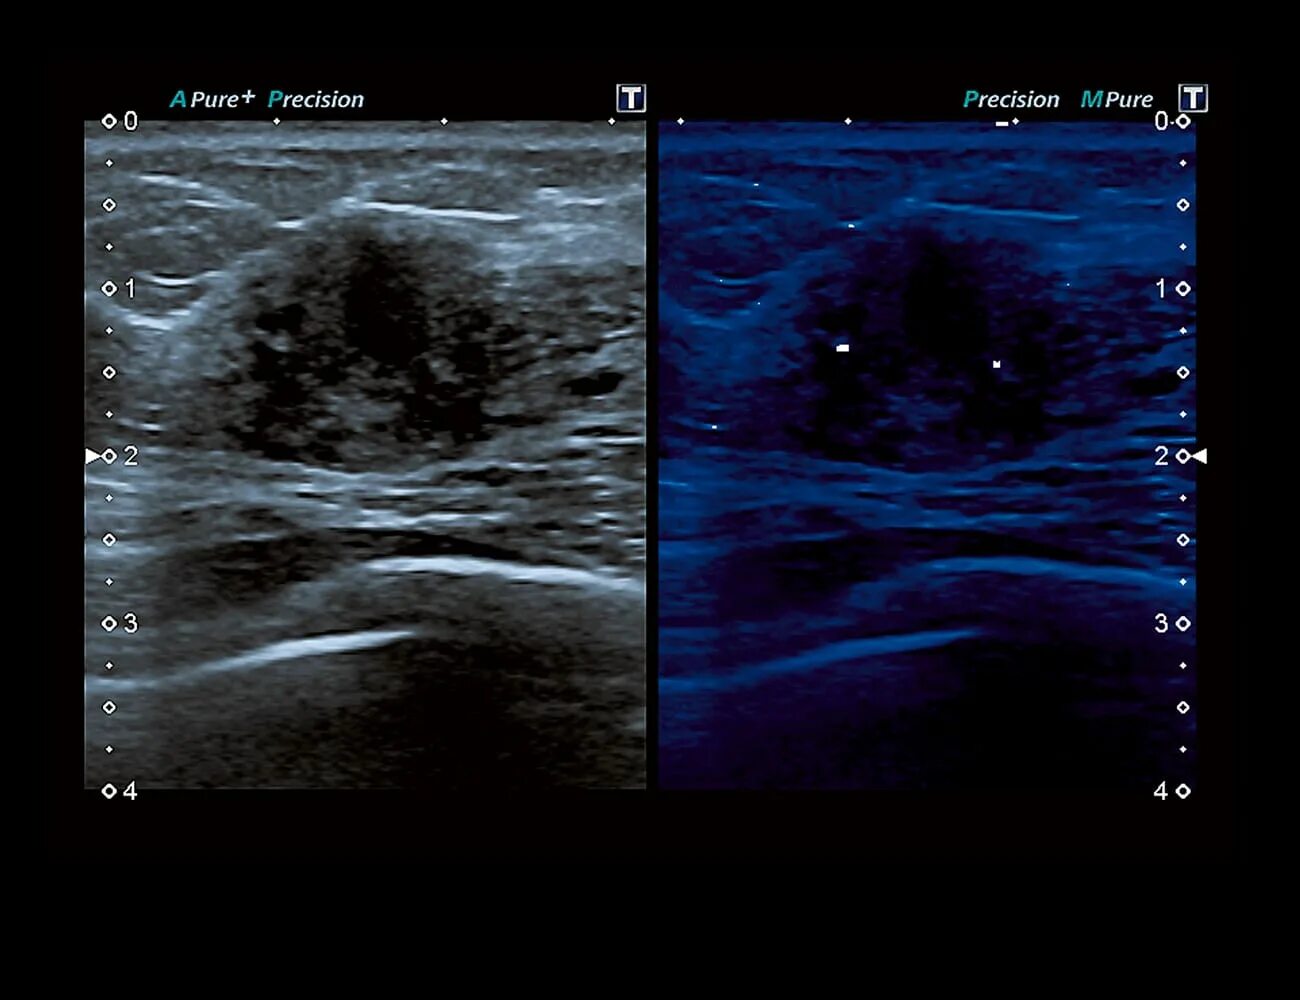

Белое пятно на узи